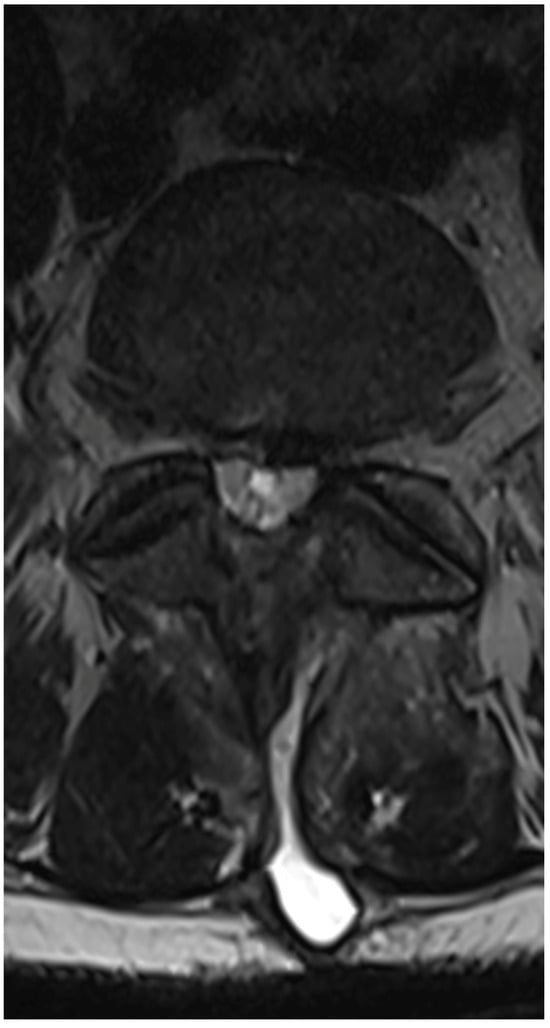

3.4. Case 1: Transient Cauda Equina Syndrome Due to Subdural Hematoma

- Case 1: Incidents of postoperative cauda equina syndrome are documented in the context of traditional surgical approaches. In our literature review, we identified a singular case of postoperative cauda equina syndrome, which, however, pertained to a patient following endoscopic intervertebral stabilization. This incident was associated with the migration of bone material into the dural sac [43]. Our case suggests that previous surgery, leading to scarring and adhesions, and anatomical challenges such as steep and large facet joints, might have contributed to the complication by complicating root mobilization and endoscope trajectory.